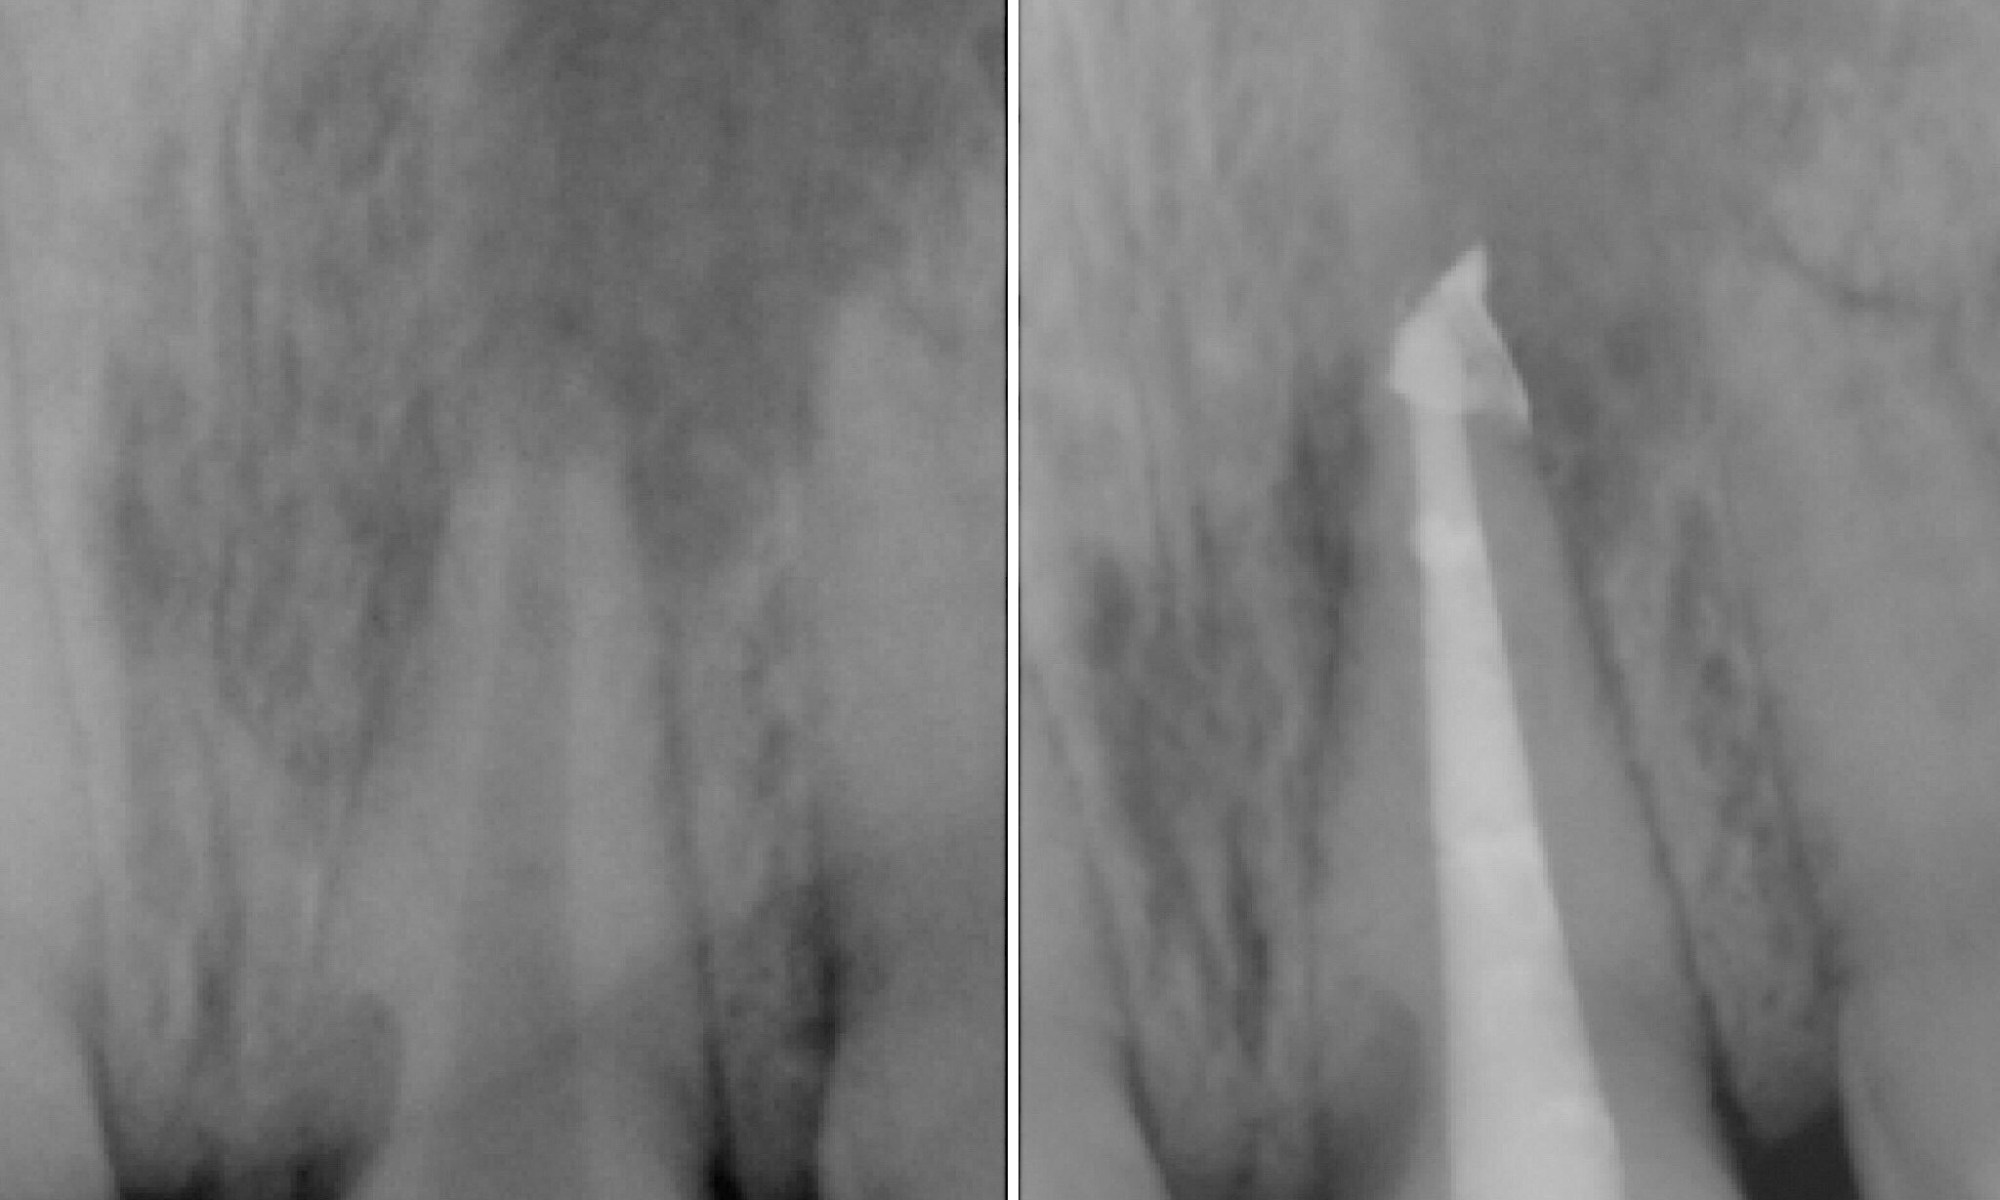

Trauma CAN cause infection. After suffering from an accidental hit to the face, this patient began to have pus draining through her gums. Root canal therapy was completed to remove the bacteria inside the tooth. It is important that the entire canal is cleaned out and sealed.